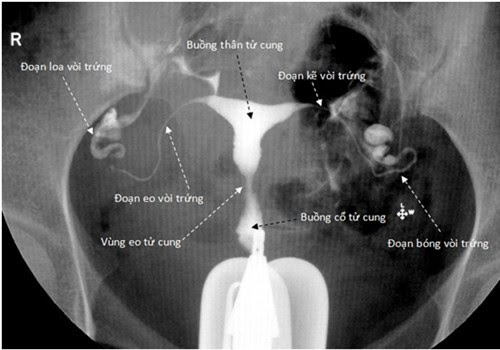

Chụp X-quang hoặc siêu âm để xác định nguyên nhân của vô kinh;

Chụp CT vùng bụng và vùng xương chậu nếu nghi ngờ có hiện tượng bất thường của tử cung hoặc buồng trứng.